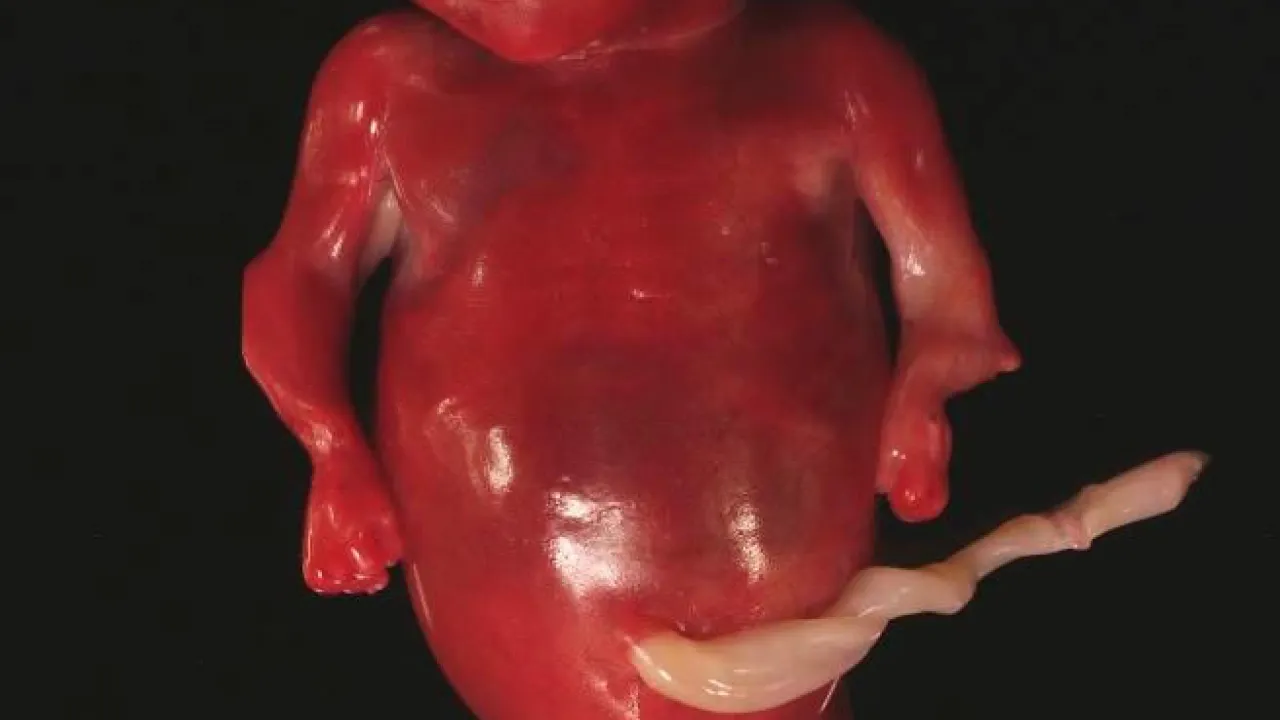

Cranium, Twin reversed arterial profusion sequence

Foot, Twin reversed arterial profusion sequence

Skeleton and body morphology, Twin reversed arterial profusion sequence